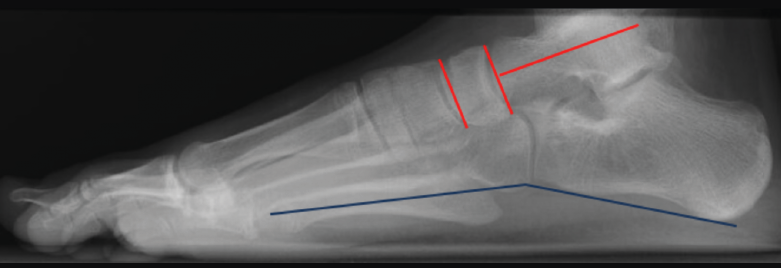

Radiografía lateral del pie en carga (Figura 6)

Figura 6. Radiografía lateral del pie en carga. A: pie normal; B: pie plano. Ángulo de Meary (rojo). Ángulo de Costa-Bartani (azul). Calcaneal pitch angle (negro).

- Ángulo de Costa-Bartani: mide el arco longitudinal medial y está definido por 2 líneas que unen respectivamente los puntos más bajos del calcáneo, el astrágalo y la cabeza del primer metatarsiano, siendo normal entre 125 y 135°. Aumentado en PPV, es una medida del aplanamiento del arco interno.

- Ángulo de Meary (ángulo lateral del astrágalo-primer metatarsiano): su valor normal es entre 0 y 10°. Este ángulo también es una medida del aplanamiento del arco interno y está alterado en los diferentes patrones de pie plano (media de 35°).

- Calcaneal pitch angle (ángulo de inclinación del calcáneo): es normal entre 20 y 30°. Está disminuido en todos los patrones de pie plano, excepto en el patrón de pie plano cavo, que está aumentado.

Para determinar el patrón anatómico del pie plano(3), se valora en la radiografía lateral en carga dónde está el vértice de la deformidad mediante los siguientes ángulos (Figura 7):

Figura 7. Radiografía lateral en carga de un pie normal. Ángulos utilizados para determinar el patrón anatómico del pie (rojo). El ángulo entre los puntos inferiores del calcáneo y el quinto metatarsiano (azul), si está disminuido, nos orienta para el diagnóstico de pie plano cavo.

• Ángulo entre el eje longitudinal del astrágalo y la superficie articular navicular (normal: 90°).

• Ángulo entre las superficies articulares del navicular y la superficie articular distal del primer cuneiforme (N1C) (normal: 0°).

• Ángulo entre los puntos inferiores del calcáneo y el 5° metatarsiano (normal: 160°).